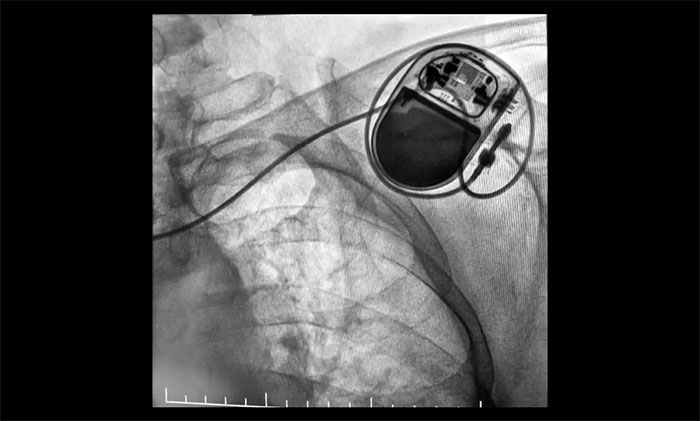

包括心臟電復(fù)律(用于房顫、室速等緊急情況)、射頻消融術(shù)(適用于房顫、室上速的治療)、植入心臟起搏器(適用于嚴重心動過緩)或埋藏式心臟除顫器(ICD)(針對高猝死風(fēng)險者)。

▲ 心臟起搏器順利植入

近日,上海藍十字腦科醫(yī)院成功完成首例永久性心臟起搏器植入手術(shù)。該患者為老年女性,因陣發(fā)性房顫伴顯著房性心律失常及竇房結(jié)功能不良,存在心跳驟停高風(fēng)險。手術(shù)在DSA引導(dǎo)下耗時40分鐘順利完成,出血不足5毫升,術(shù)后起搏器功能良好,患者正在康復(fù)中。